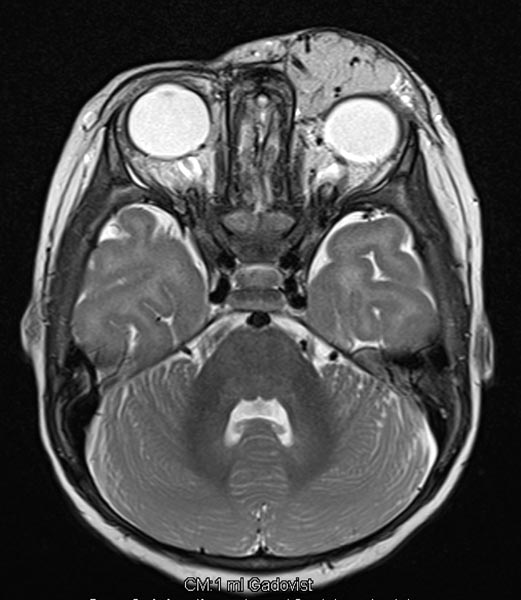

T2-gewichtete axiale MRT mit Fettsättigung. Die Raumforderung medial am linken Auge ist relativ homogen hyperintens und scharf abgrenzbar zum umgebenden Rand. Als Zeichen der starken arteriellen Durchblutung sieht man einige schwarze, signallose arterielle Gefäße in der Läsion („flow voids“). Auch dies ist typisch für ein infantiles Hämangiom.